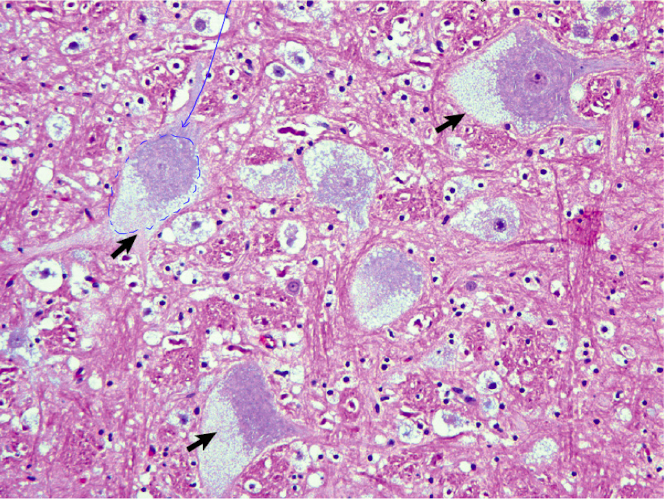

Name the process that is occuring in the tissue below:

AA Amyloidosis

Extracellular eosinophillic deposit > compress tissue > cell atrophy/death > loss of function